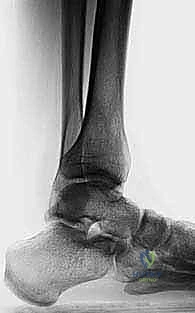

الحالة الأولى: تصحيح تشوه ما بعد كسر قديم

مريض يبلغ من العمر 42 عاماً، تعرض لكسر في الساق قبل 5 سنوات التئم بشكل خاطئ، مما أدى إلى تقوس شديد للداخل (Varus) وألم مستمر يمنعه من العمل. بعد تقييم دقيق من قبل الأستاذ الدكتور محمد هطيف، تم إجراء جراحة قطع عظم الساق فوق الكاحل بتقنية الوتد المفتوح. بعد 4 أشهر من الجراحة والتأهيل، عاد المريض لعمله الميداني بمحور ساق مستقيم تماماً وبدون أي ألم.